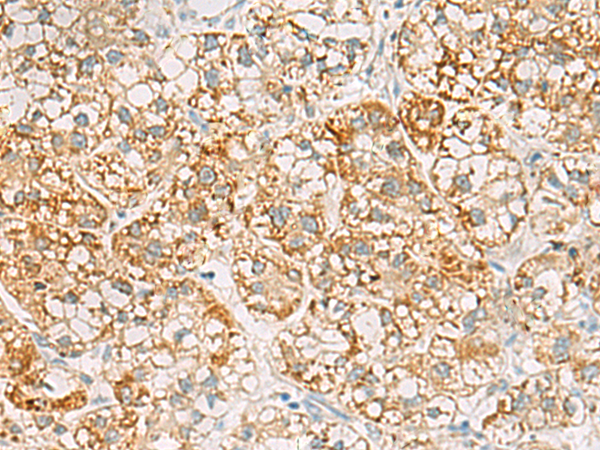

分类: 科研抗体货号: P03228别名: RAY应用: IHC反应种属: Human, Mouse, Rat